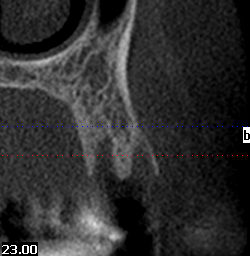

patiente adressée dont l'extraction de 24 a eu lieu il y a 9 semaines sans comblement ni tentative de recouvrement. J'ai prévu l'implantation la semaine prochaine.